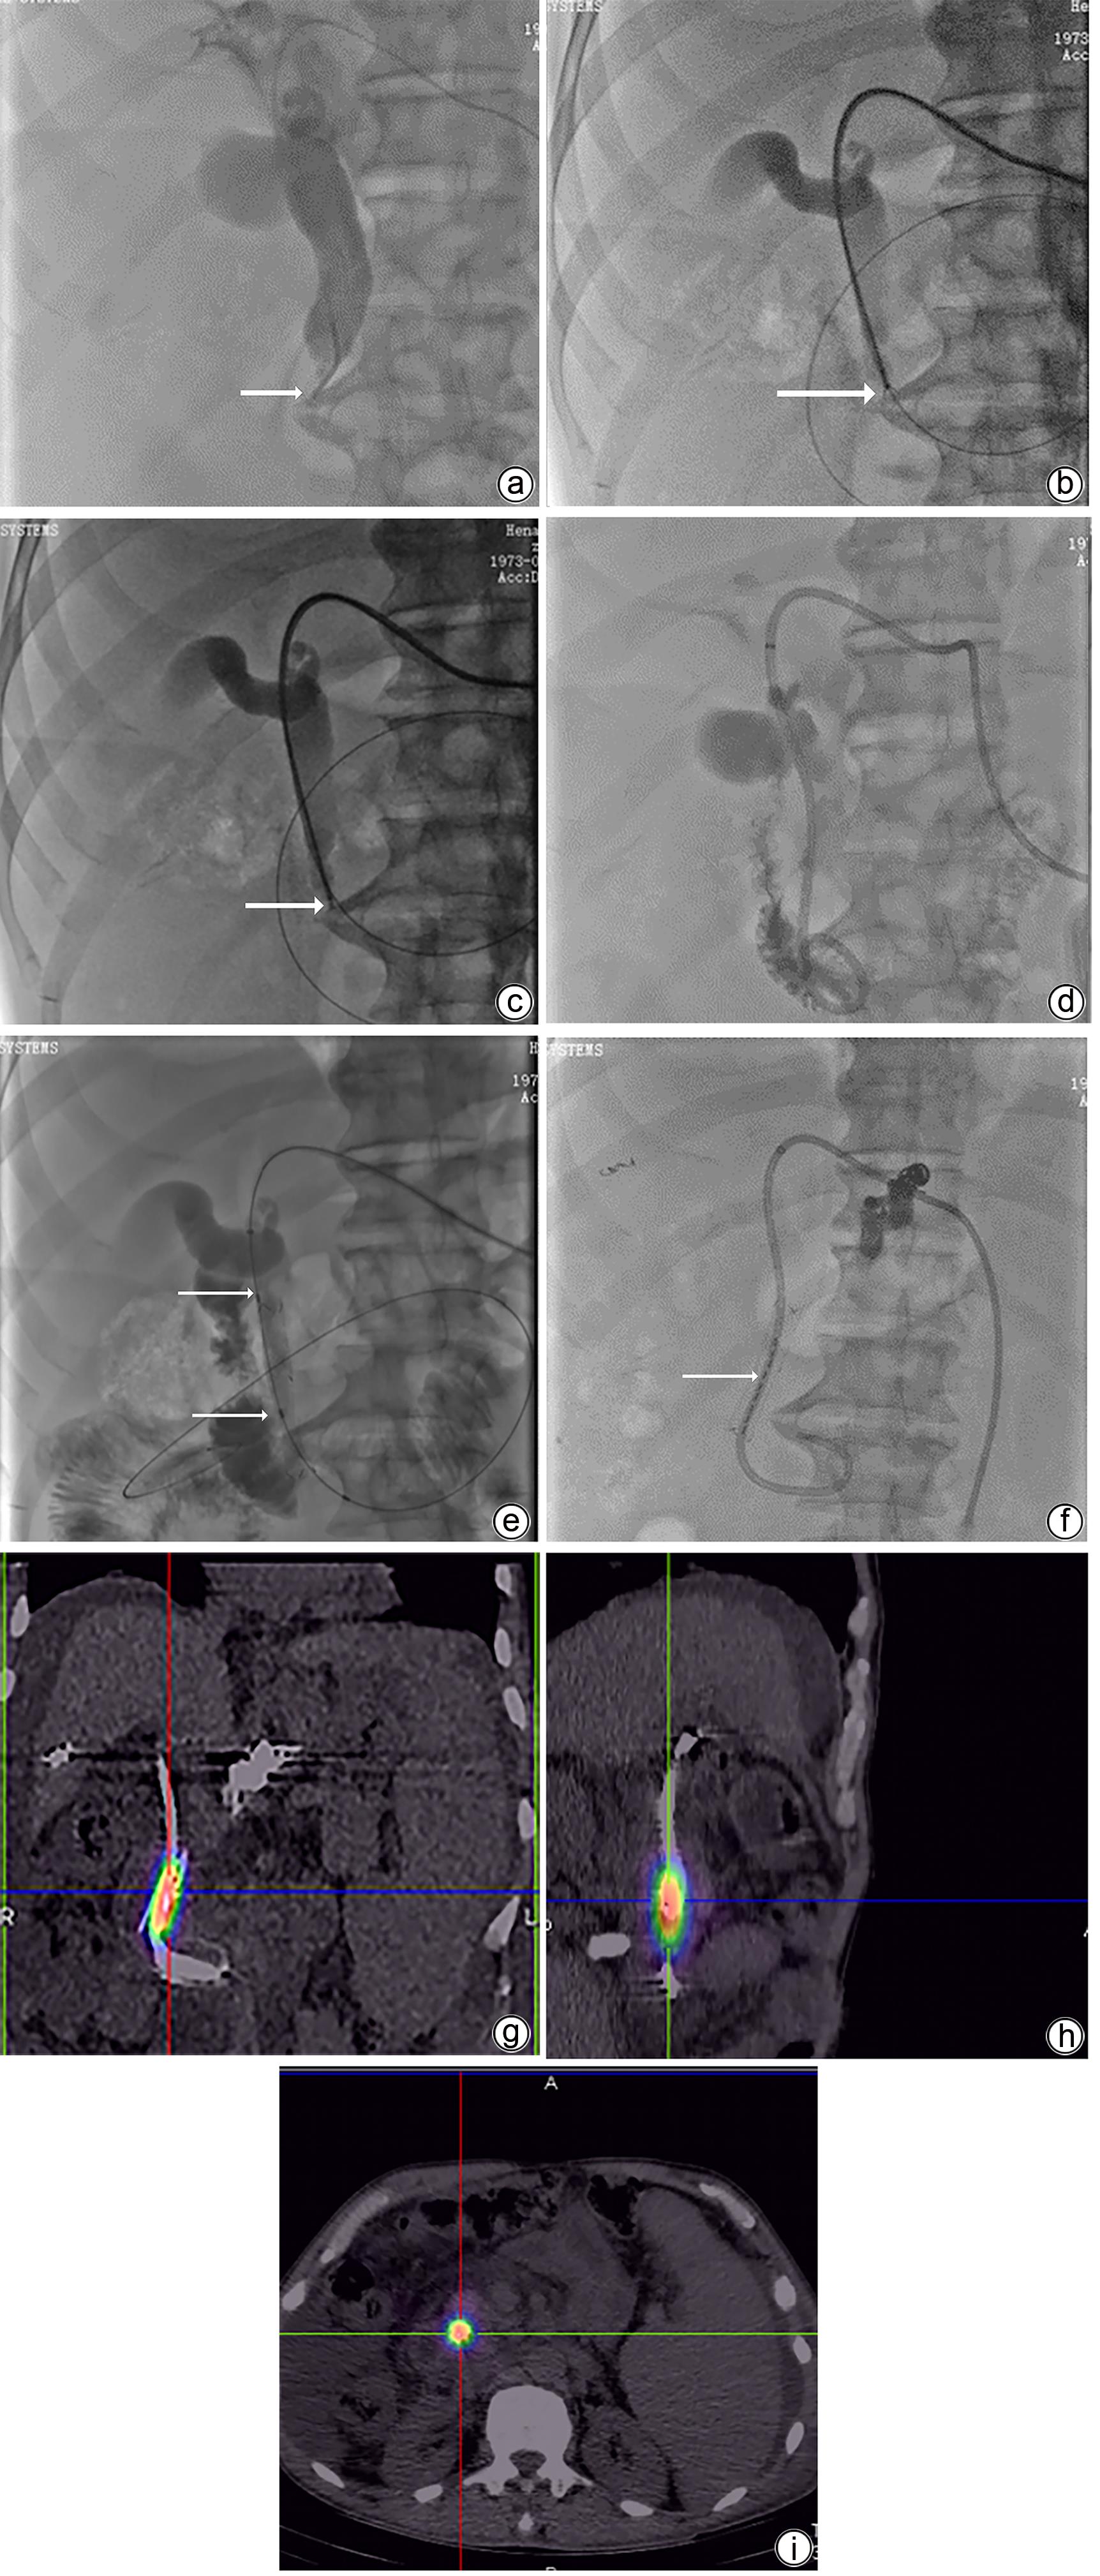

Efficacy and safety of 125I intraluminal irradiation combined with lenvatinib in treatment of progressive extrahepatic cholangiocarcinoma

Xingshu ZHU, Pengfei CHEN, Mengfan ZHANG, Fangzheng LI, Jinwei CHEN, Wenguang ZHANG, Xuhua DUAN, Jianzhuang REN, Xinwei HAN

2023, 39(10): 2406-2412. DOI: 10.3969/j.issn.1001-5256.2023.10.019

Abstract(1027) HTML (306) PDF (1005KB)(49)

Abstract:

Objective  To investigate the efficacy and safety of 125I intraluminal irradiation combined with lenvatinib in the treatment of progressive extrahepatic cholangiocarcinoma.  Methods  A retrospective analysis was performed for 25 patients with progressive extrahepatic cholangiocarcinoma who attended Department of Interventional Radiology, The First Affiliated Hospital of Zhengzhou University, from January 2018 to November 2021, and according to the treatment modality, they were divided into combination group with 13 patients (125I intraluminal irradiation combined with lenvatinib) and control group (125I intraluminal irradiation alone). The two groups were compared in terms of technical success rates, changes in liver function, stent patency, survival time, and incidence rates of adverse events. The independent-samples t test was used for comparison of normally distributed continuous data between two groups, and the Wilcoxon rank-sum test was used for comparison of continuous data with skewed distribution between two groups; the Fisher’s exact test was used for comparison of categorical data between groups. The Kaplan-Meier method and the log-rank test were used to evaluate survival time and stent patency.  Results  All patients had successful implantation of biliary stents and 125I particles, with a technical success rate of 100%. After 1 month of treatment, both groups had significant improvements in the serum levels of total bilirubin, direct bilirubin, alanine aminotransferase, and aspartate aminotransferase (all P<0.05). There were significant differences between the control group and the combination group in the duration of stent patency (7.0 months vs 9.5 months, P=0.022) and median survival time (11.5 months vs 15.6 months, P=0.008). There were no intolerable adverse events in the combination group during treatment.  Conclusion  Compared with 125I intraluminal irradiation alone, 125I intraluminal irradiation combined with lenvatinib has better efficacy and is a safe and effective treatment regimen for progressive extrahepatic cholangiocarcinoma.